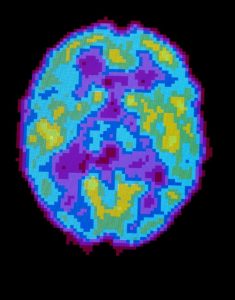

A PET scan of a brain during normal sleep. Two scientists say sleep may help the brain prune back unneeded synapses.